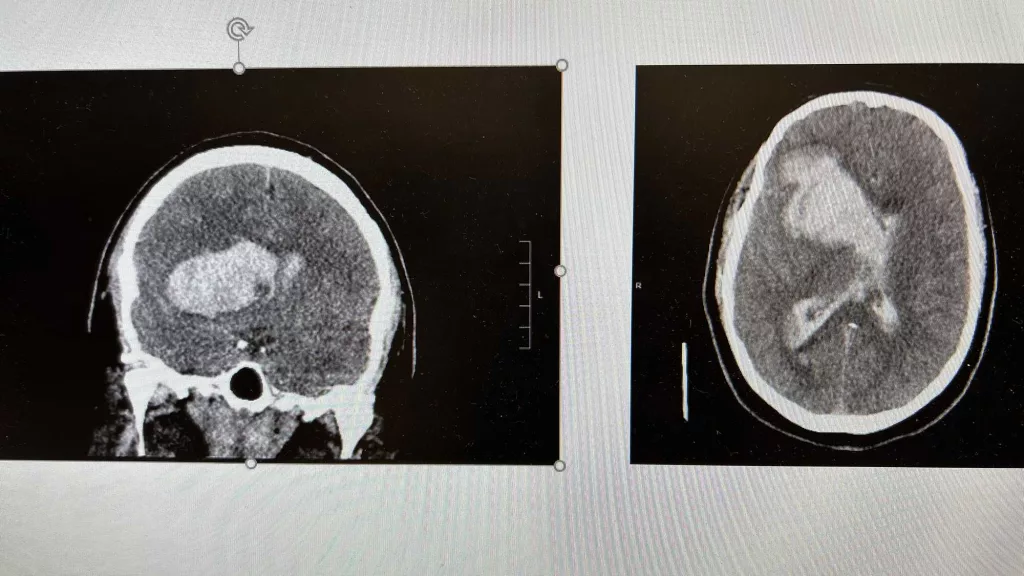

Every second counts to survive a stroke. Here are the signs you need to know and watch out for

An American has a stroke every 40 seconds, and every four minutes, someone dies from stroke. See the signs to watch for, and know why minutes matter.